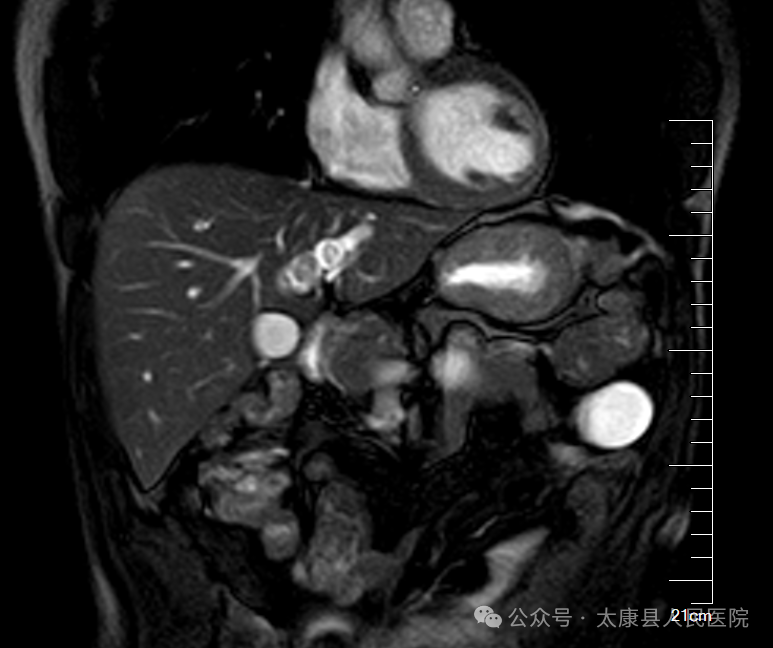

患者因"间断腹痛1天余"入院,经CT及MRCP检查诊断为:肝内胆管多发结石并胆管扩张、阑尾炎若采用传统开腹手术,需25cm以上切口,创伤大、恢复慢。

手术过程中,刘进学主任凭借丰富的临床经验和娴熟的操作技巧,联合麻醉科副主任医师王晓东、手术室护士长张翠华等医护人员精准完成“腹腔镜下肝左外叶切除+胆管切开取石T管引流术+胆道镜探查+胆囊切除术+阑尾切除术”等多个手术步骤。术后复查显示肝内结石清除干净,患者恢复良好。